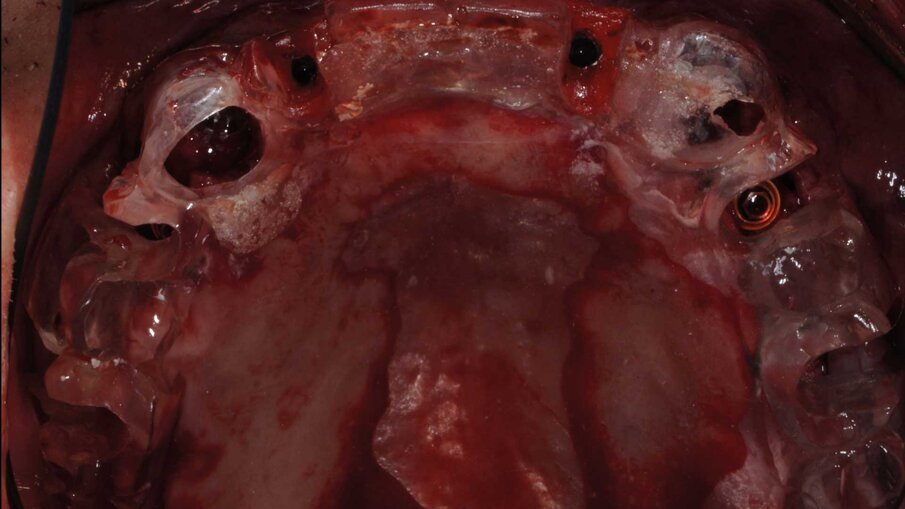

La fase chirurgica fu eseguita circa due mesi dopo le estrazioni. Al paziente fu somministrata terapia antibiotica preventiva dalla mattina dell’intervento chirurgico e protratta per sei giorni. Fu somministrata anestesia locale con Articaina 1:100000 e adrenalina al 2%. Furono scollati lembi a tutto spessore e furono inseriti sei impianti BTI Core in ogni mascellare. Fu eseguito prima l’intervento sul superiore e dopo un mese sull’inferiore su richiesta del paziente che aveva paura di postumi eccessivi. Gli impianti furono posizionati con l’ausilio delle mascherine chirurgiche (Figg. 8, 9) che furono usate per la registrazione della posizione degli impianti secondo la metodica del modello modificato descritta dal dott. Lionello Biscaro. La posizione risultava molto accurata grazie alla stabilizzazione offerta dai canini residui che furono estratti subito dopo l’inserzione degli impianti per consentire la registrazione della posizione relativa degli impianti (Figg. 10, 11). In particolare nella posizione del dente 16 fu inserito un impianto BTI Universal-Plus 5 mm di diametro

x 4,5 di lunghezza, in posizione 26 un impianto BTI Core 3,75 x 6,5 mentre in posizione 36 e 46 furono inseriti due impianti BTI Core 4,75 x 4,5. La superficie UnicCa degli impianti fu bagnata con frazione F2 ottenuta dal plasma per centrifugazione del sangue del paziente. Furono avvitati i pilastri Multi-Im e furono fatte le registrazioni necessarie a comunicare al tecnico la posizione degli impianti rispetto ai modelli già montati e la posizione reciproca degli impianti, secondo la tecnica del modello modificato citata precedentemente. I pilastri di guarigione furono avvitati, le suture applicate e il paziente fu dismesso.